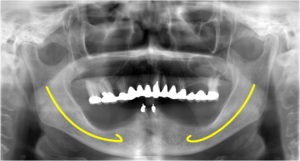

これは先日行った症例です。患者さんは、7年前に私が作った下の入れ歯を使っていらしたのですが、最近残りの2本の歯がグラグラしてきたために、インプラントを決断されました。

これまでの入れ歯でもそこそこ咬めるとおっしゃって頂いたのですが、やはりもっと咬めるようになりたいという希望が強くあったようです。そこで、患者さんが取り外しできるような入れ歯タイプではなく、取り外しのできないブリッジタイプをお勧めしました。

普通、インプラントを入れたら骨に結合するまで3〜6ヶ月待ってからでないと負荷をかけられないのですが、4本以上のインプラントを確実に固定させ、それを仮歯でしっかりと連結することで、骨との結合を待つことなく負荷をかけることが可能となります。